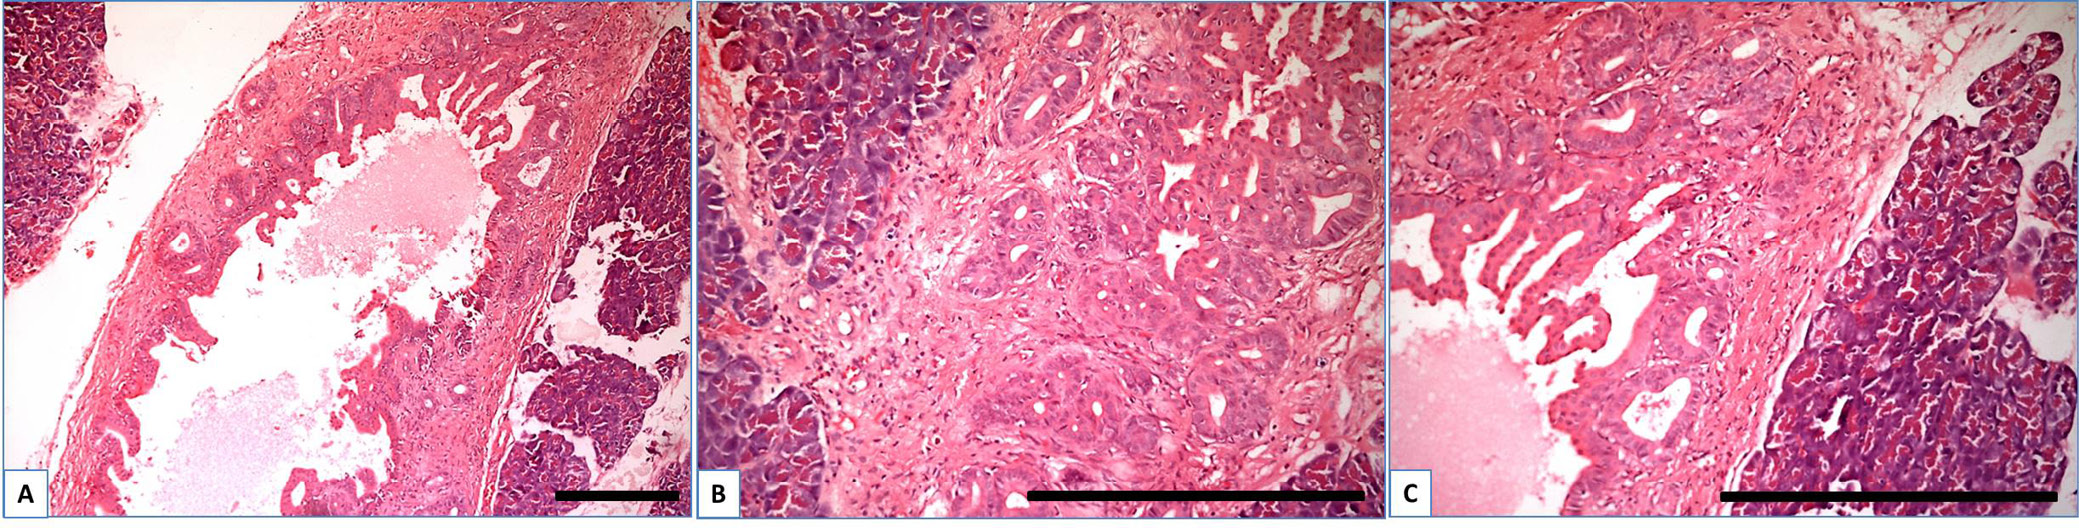

The changes observed in the ductal part were accompanied by corresponding changes in the exocrine acinar part (Figure 4). The CP group (Figure 4B) exhibited significant morphological heterogeneity in the acini, including loss of polarization in some acini and a notable difference between the eosinophilic apical part and the basophilic basal part. Conversely, the CP + DM group demonstrated acinar-ductal metaplasia through intermediate mucinous cells (Figure 4C).

As shown above, in the pancreas of rats of the CP + DM group, we observed the development of changes (ductal dysplasia, pronounced acinar metaplasia, formation of glands in the fibrotic tissue of the duct, proliferation of the epithelium of glands with severe dysplasia, appearance of papillary and cribriform structures) corresponding to high and moderate ductal dysplasia (PanIN-2 and PanIN-3). These changes are direct predictors of pancreas adenocarcinoma. The impairment of PanIN represents a pathway to the development of PC and directly to ductal adenocarcinoma. This conclusion has been corroborated in several studies.45, 46